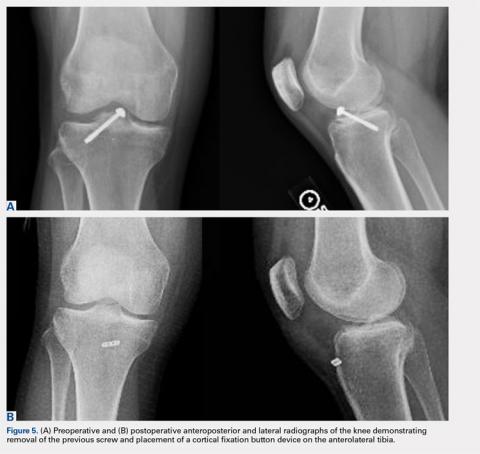

A looped passing wire was directed up the previously placed cannulas, and 1 suture was shuttled down each tunnel. The sutures were securely tied down over a bony bridge with a cortical fixation button on the anterolateral tibia. This was visualized arthroscopically to ensure proper positioning and tension of the root to its native footprint (Figure 4). A comparison of preoperative and postoperative anteroposterior and lateral knee radiographs is shown in Figures 5A, 5B.Continue to: Postoperatively, the patient was placed...